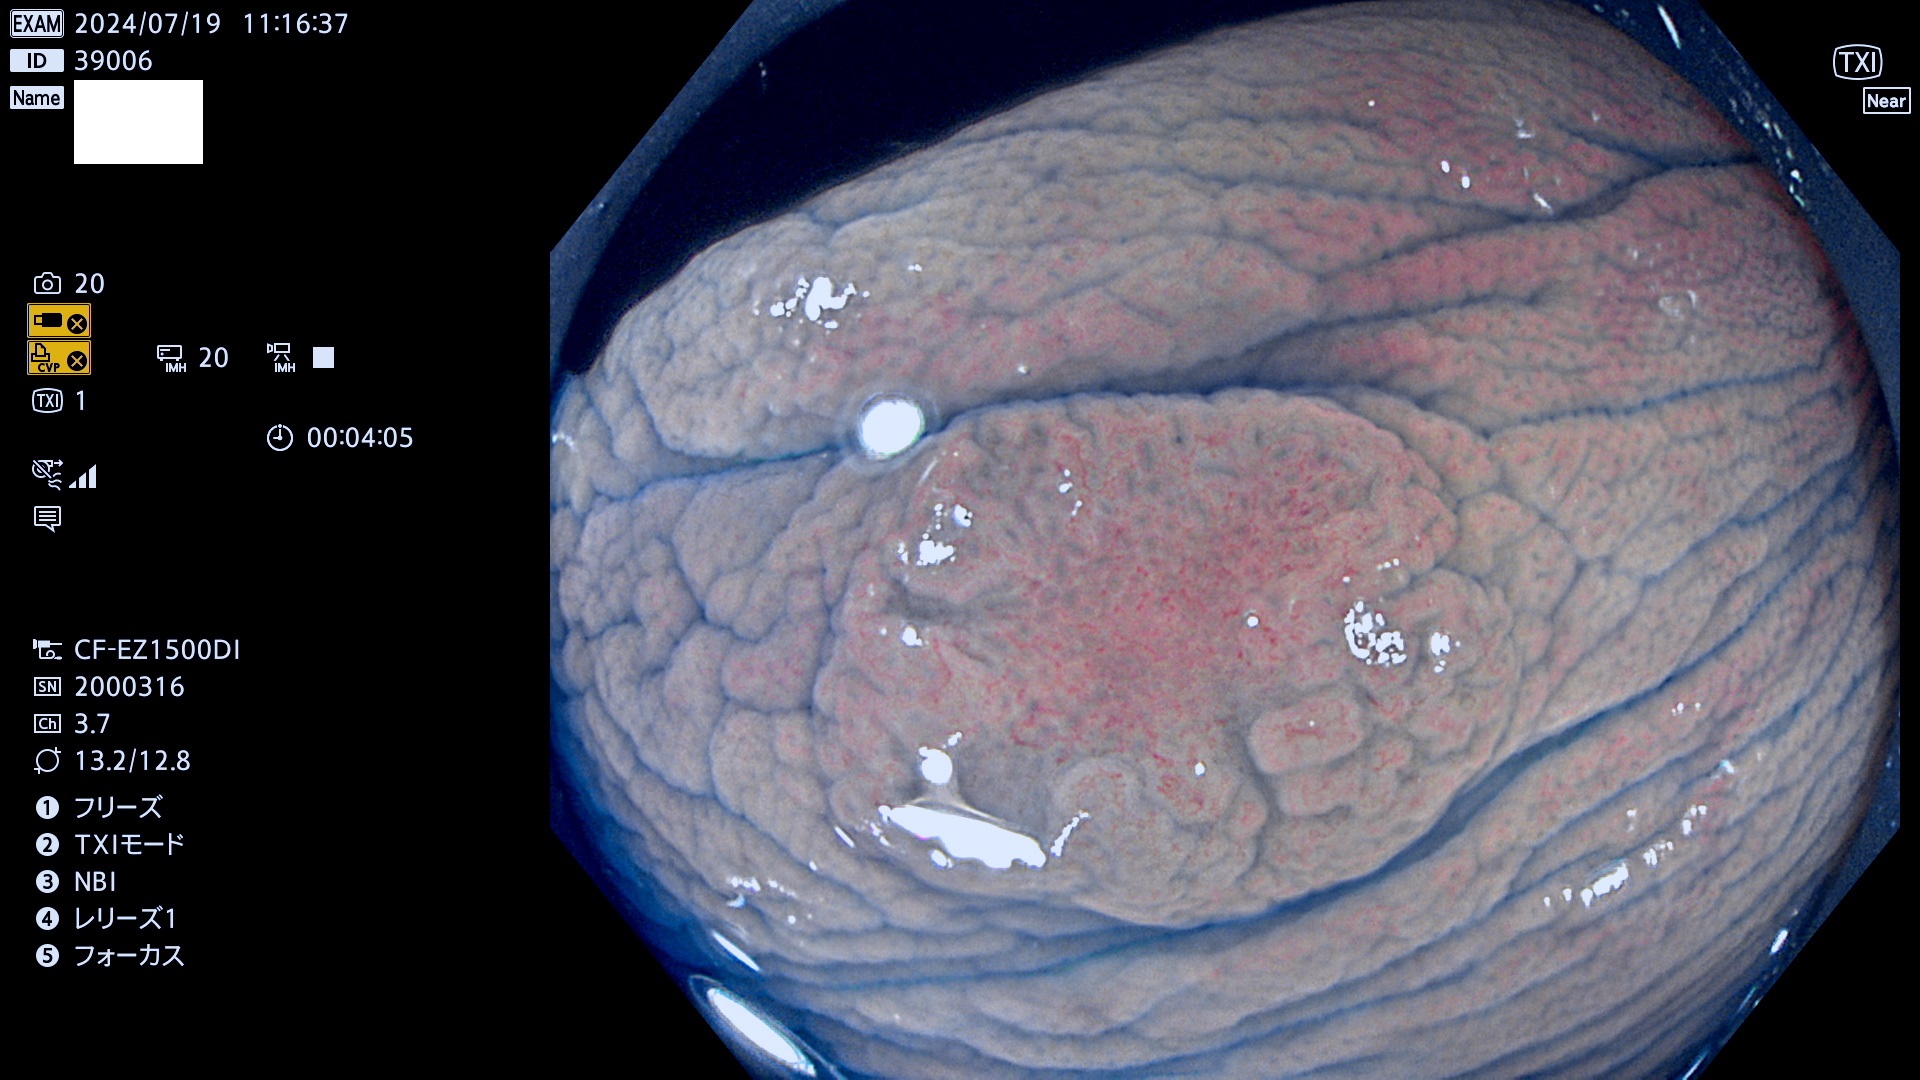

今週のUb、Uc型腺腫

完全に平坦な物をUb、陥凹している物をUcと呼びます。最も発見が難しく危険な病変です。

毎週の検査(木・金・土・日)に発見されたUb、Uc型・腺腫を、その週の日曜の夜にUPし1週間、提示します。

抽出の対象期間 2024年7月18日〜7月21の4日間(25件の検査)6件 (6/25=24%)